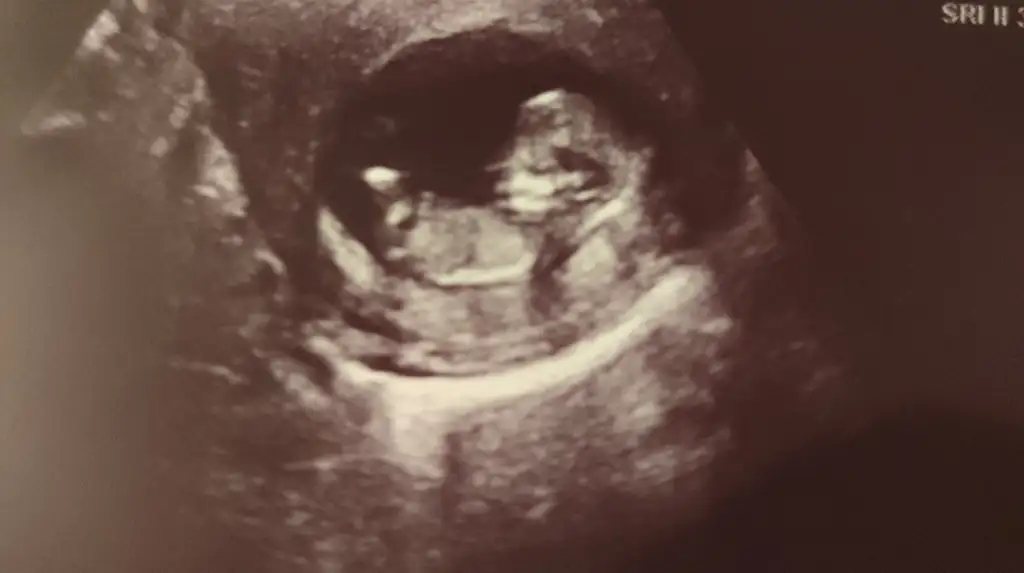

Kaç haftalık acaba bu ultrasonda bebişinizMerhaba ultrasona göre cinsiyet tahmini yapabilecek var mı Eki Görüntüle 3672273